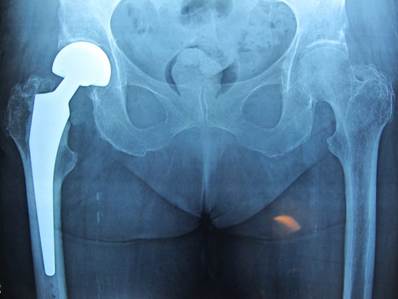

Σχετικά με τα απαρεκτόπιστα κατάγματα του αυχένα του μηριαίου οστού αντιμετωπίζονται κατά κανόνα με κοχλίωση, ενώ τα παρεκτοπισμένα με αρθροπλαστική συνήθως ημιαρθροπλαστική ή ολική αρθροπλαστική ισχίου σε νεότερους και δραστήριους ασθενείς. Τα διατροχαντήρια και υποτροχαντήρια κατάγματα αντιμετωπίζονται με ανοικτή ανάταξη και εσωτερική οστεοσύνθεση, κυρίως με ενδομυελικό ήλο ισχίου ή, σε σταθερές περιπτώσεις, με ολισθαίνοντα κοχλία. Η μη χειρουργική αντιμετώπιση είναι εξαιρετικά περιορισμένη και αφορά μόνο πολύ σταθερά κατάγματα ή ασθενείς με ιδιαίτερα επιβαρυμένο ιατρικό ιστορικό και ελάχιστη προϋπάρχουσα κινητικότητα.